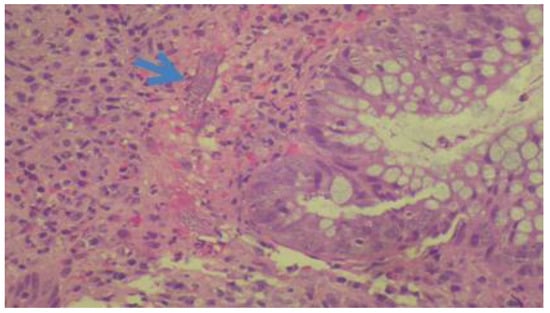

| 2 | M, 72 | March 2015 | Shipper | COPD, Corticosteroids | Hyperinfection syndrome | Yes (2400) | Larvae in large intestine biopsy and fecal samples Serology +(8.88) | Ivermectin + albendazole | Death |

| 7 | M, 71 | November 2016 | Gardener | Colon adenocarcinoma | Asymptomatic | Yes (2400) | Larvae in large intestine biopsy and fecal samples Serology +(8.88) | Ivermectin | Seroreversion |